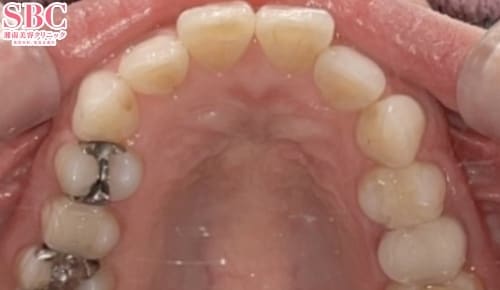

施術前

歯のガタツキや重なりが気になるとのこと・・・